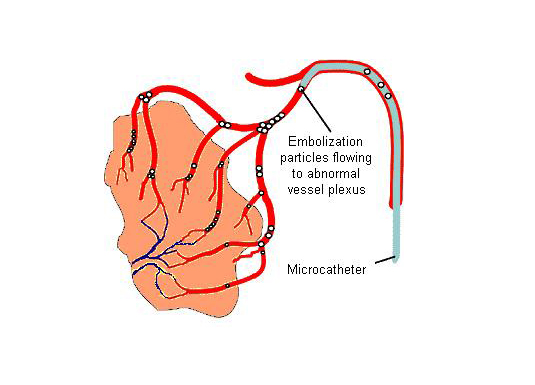

The above procedures are called revascularization procedures in which the diseases reduce the blood flow to brain and we improve the flow to brain. There are few conditions where there is increased blood flow and we attempt reduce the flow. This procedure is called embolization. The conditions are Arterio-venous fistula and arterio-venous malformations.

Spinal angiogram is done to assess the blood supply to the spinal cord. Below is a case of tumor with increased blood supply from a spinal artery. As the surgical removal is associated with increased blood loss, the blood supply was blocked of endovascularly.